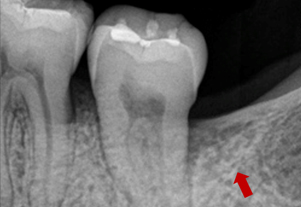

症例3(再生療法)

Before

After

- POINT

- 他院で歯周病の治療をしていましたが、なかなか歯周病が改善されず、セカンドオピニオンにて来院された患者様です。歯周病の進行した部分に再生療法を行い(エムドゲインを使った歯茎の手術)ホームケアを徹底することで改善されました。

今後も継続したメインテナンスが必要です。